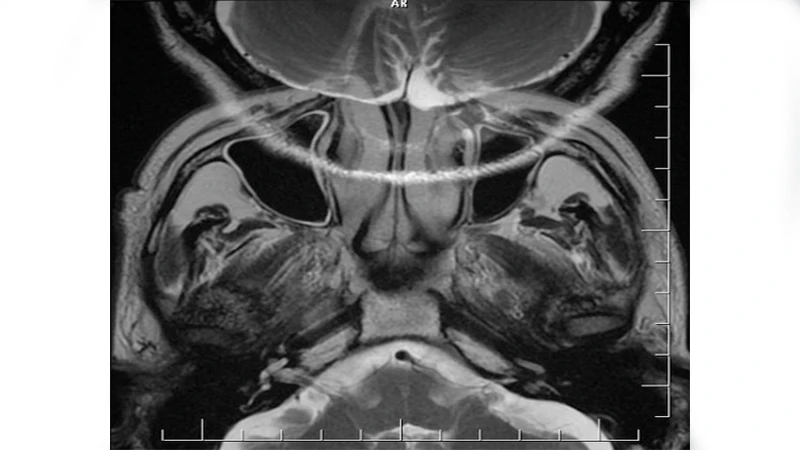

3. Aliasing or "Wrap-Around" Artifact (MRI)

This is a specific MRI artifact that occurs when the Field of View (FOV) is set too small for the body part being scanned. Anatomy that is outside the FOV gets "wrapped around" and appears on the opposite side of the image.

• Appearance: A portion of the anatomy (e.g., the nose in a brain scan, or an arm in an abdomen scan) appears superimposed on the other side of the image.

• Cause: The scanner misinterprets the spatial location of signals coming from outside the prescribed FOV.

• Solution:

• Increase FOV: The simplest fix is to ensure the Field of View is large enough to encompass the entire anatomy being imaged.

• Oversampling/No Phase Wrap: Most modern scanners have built-in software options (often called "oversampling" or "no phase wrap") that can be enabled to prevent this artifact without having to significantly increase the FOV.

An MRI of the head where the nose has 'wrapped around' and appears on the back of the head due to an aliasing artifact.